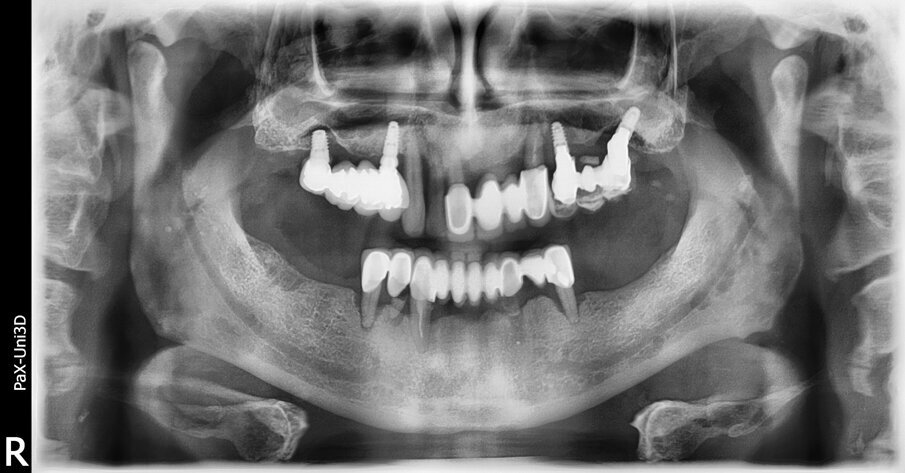

Il paziente, maschio di 66 anni, ASA 2, giunge alla nostra osservazione lamentando dolore, mobilità e disagio a carico del sestante superiore sinistro. L’esame clinico eseguito rivelava un avanzato grado di malattia parodontale, classificabile come grado IV stadio C, in accordo con la più recente classificazione delle malattie parodontali10, caratterizzato inoltre da sanguinamento gengivale spontaneo, suppurazione e una forma acuta di gengivite generalizzata. È presente una riabilitazione protesica metallo-ceramica (PFM) su elementi naturali dell’intera arcata mandibolare, mentre nel mascellare superiore sono presenti tre differenti ponti, uno su elementi naturali e due su impianti. Tutte le riabilitazioni protesiche presentano un elevata mobilità, di grado variabile tra il 2 e il 3. L’esame ortopanoramico (Fig. 1) eseguito dimostra un esteso riassorbimento osseo con presenza di difetti ossei verticali e orizzontali coinvolgente tutti gli elementi dentali residui. Si rileva anche la presenza di quattro fixture implantari nei settori mascellari posteriori. Due di queste presentano ampi difetti circonferenziali all’intero corpo dell’impianto. L’esame cone beam (Fig. 2) conferma i difetti già diagnosticati dall’ortopanoramica ed evidenzia, in aggiunta, un profondo difetto osseo esteso dal canino superiore sinistro fino a oltre il primo premolare. Alla base dei seni mascellari di destra e di sinistra è presente una cresta ossea di altezza estremamente ridotta. Il seno mascellare di sinistra, inoltre, appare completamente riempito da una reazione infiammatoria di natura iperplastica.

Fig. 1_Ortopanoramica pre-operatoria che evidenzia il grado di riassorbimento osseo.